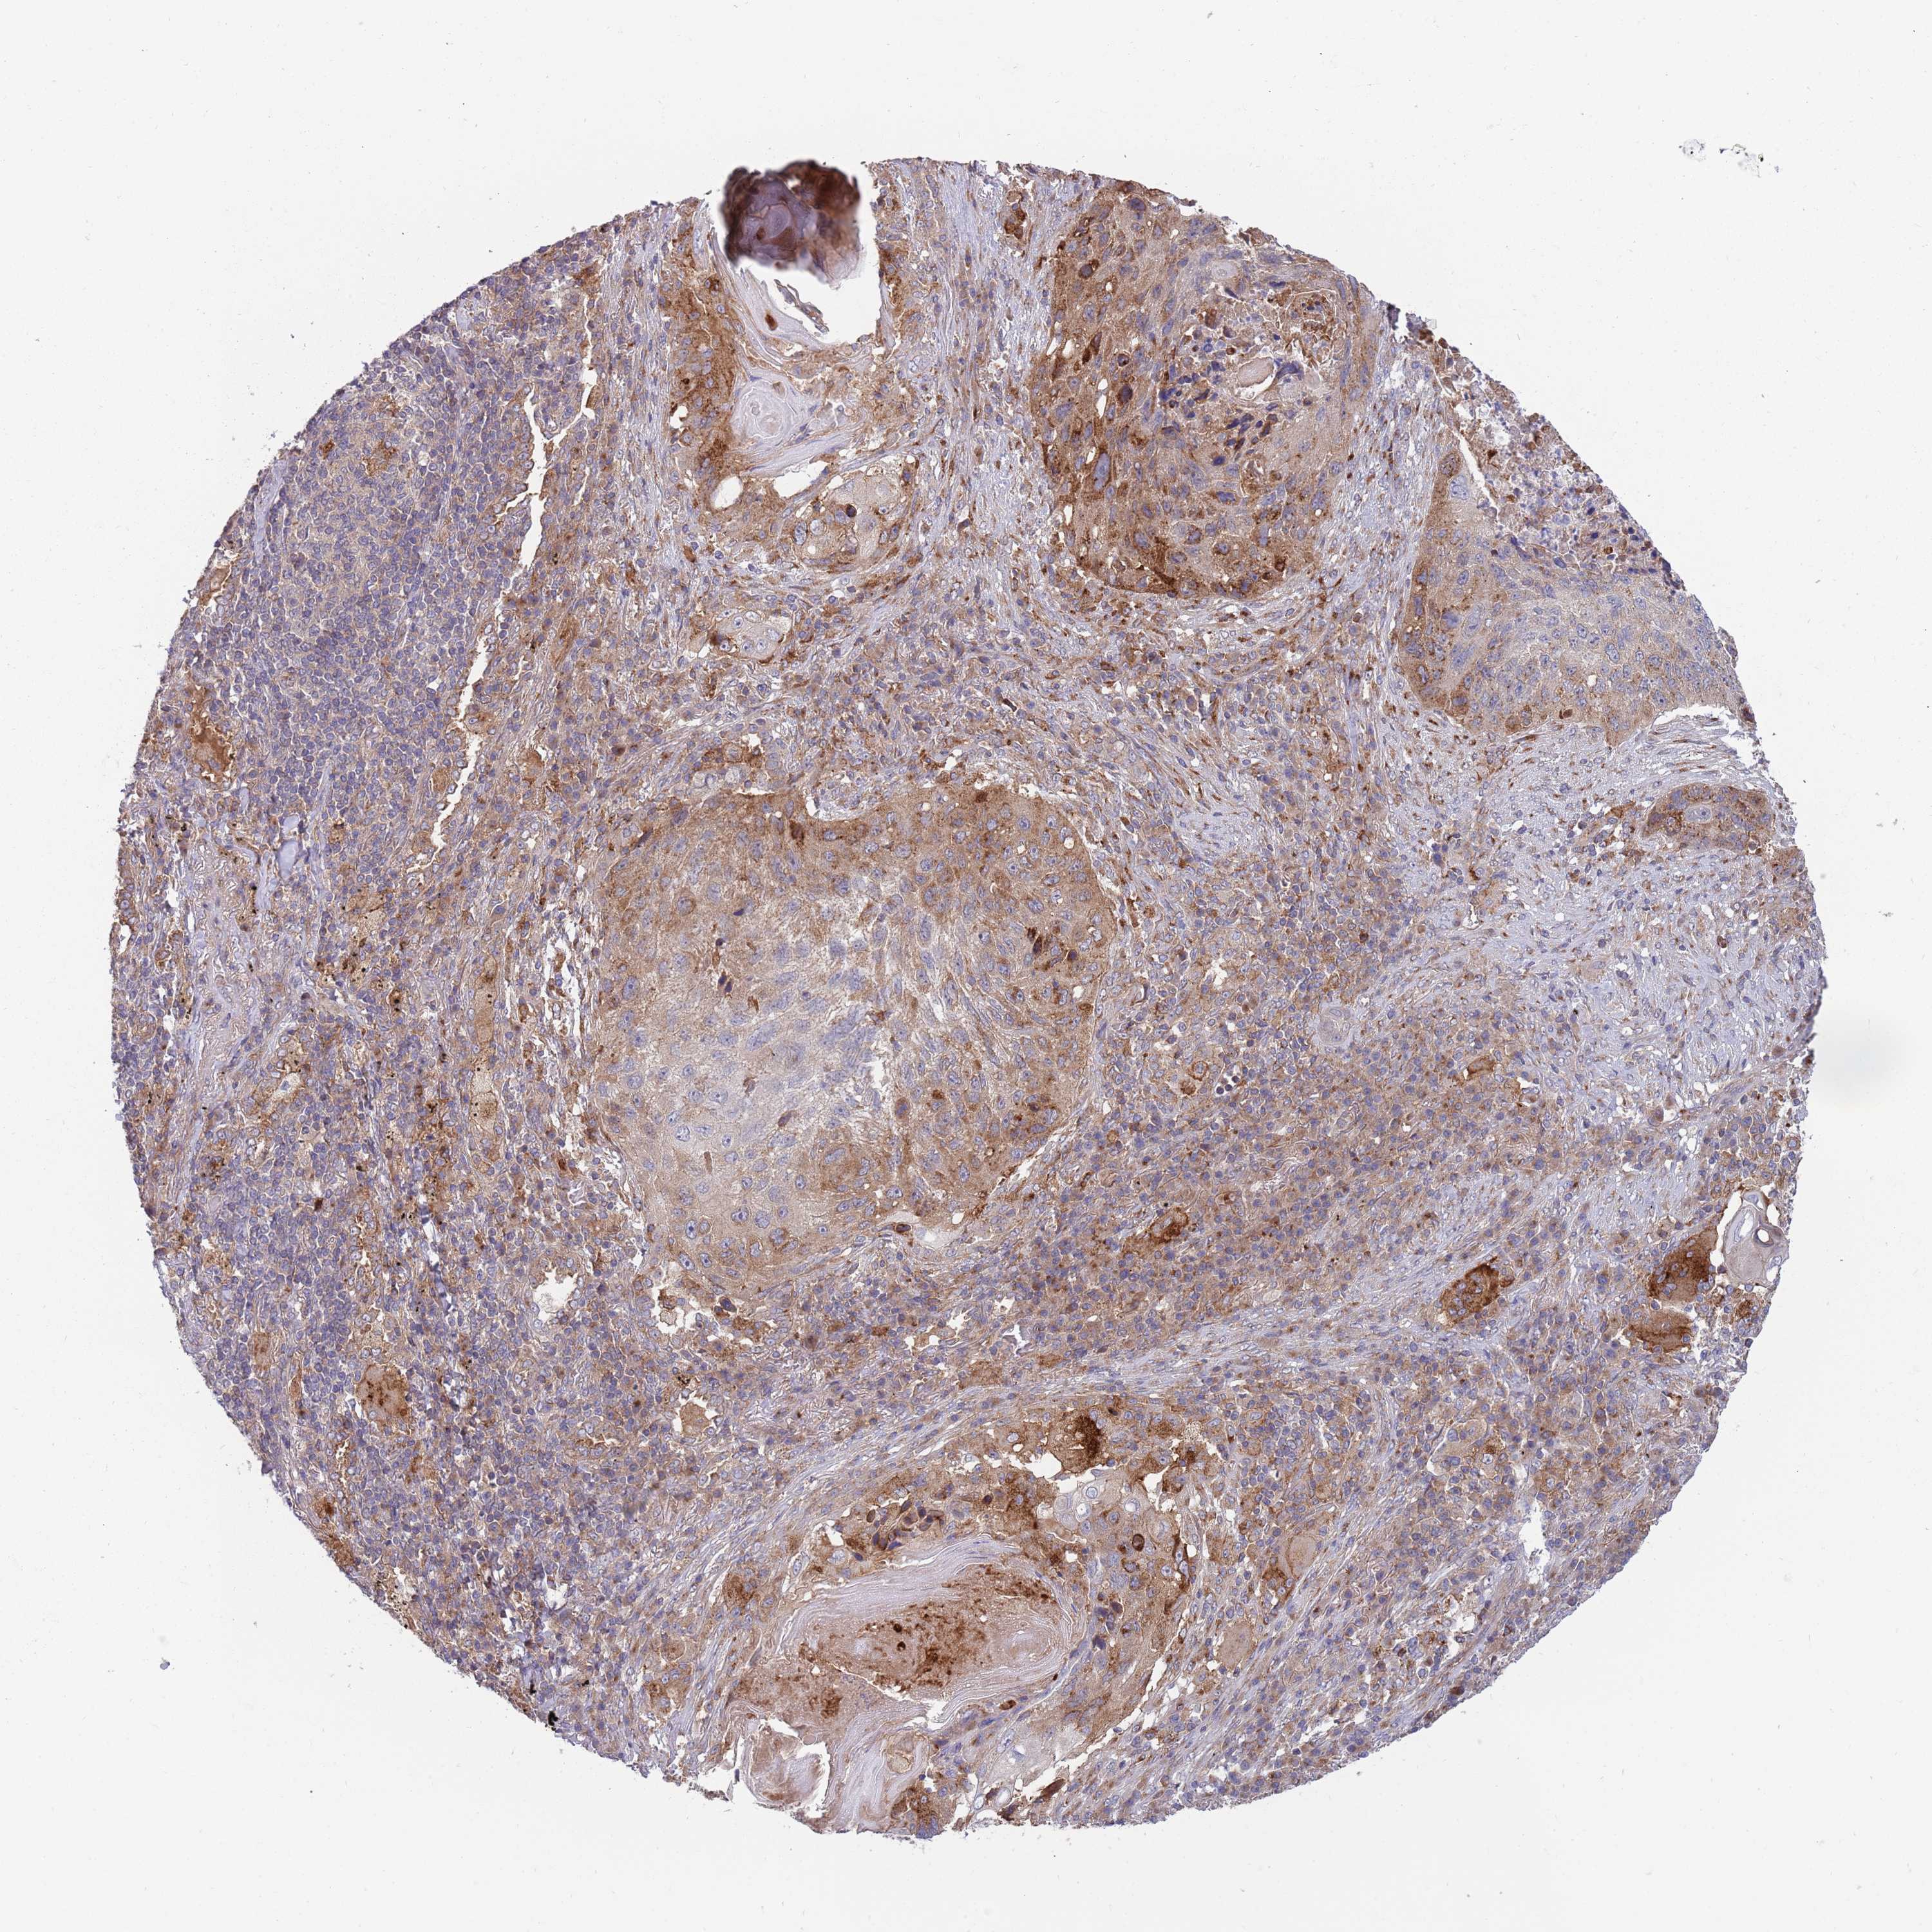

CANCER LUNG CANCER Show tissue menu

Lung cancer

Human cancer